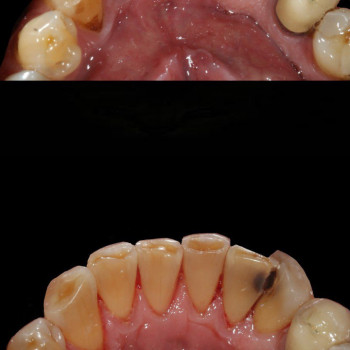

Лікування пародонтиту від 1 до 4 ступеня тяжкості у Хмельницькому Пародонтит – це запальне захворювання ясен і тканин, що утримують зуби. Без лікування воно прогресує від початкового нальоту й кровоточивості до серйозної втрати кісткової тканини та рухливості зубів. У нашій клініці ми проводимо комплексне лікування пародонтиту будь-якої стадії – від 1 до 4 ступеня тяжкості. ✔️ 1 ступінь – професійна гігієна, усунення нальоту, навчання догляду ✔️ 2 ступінь – кюретаж ясенних кишень, лікування запалення ✔️ 3 ступінь – комплексна терапія, шинирование, відновлення тканин ✔️ 4 ступінь – хірургічні методи, імплантація та протезування при втраті зубів Ми використовуємо сучасні методи: ультразвукову чистку, Air Flow, закритий кюретаж. Регулярне звернення до пародонтолога дозволяє зупинити прогресування хвороби, зберегти власні зуби та повернути здоров’я ясен. 👉 Запишіться на консультацію та лікування пародонтиту у Хмельницькому – відновіть здоров’я ротової порожнини на будь-якій стадії захворювання!

Відповідь: Виділяють 4 ступені: від легкої форми з нальотом і кровоточивістю до важкої – із втратою кісткової тканини та рухливими зубами.

Відповідь: Лікування включає професійну гігієну, кюретаж, комплексну терапію, шинування, а на пізніх стадіях – хірургію та протезування.